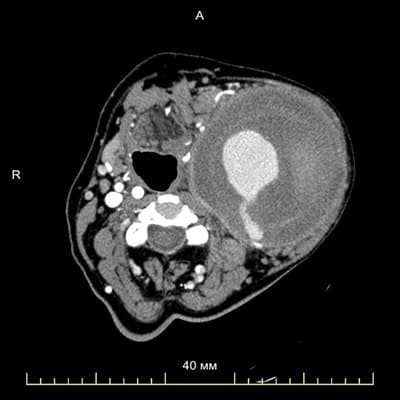

В отделении сосудистой хирургии Гродненской университетской клиники ежегодно выполняют не менее 700 вмешательств на разных участках кровотока. Хирургами отделения была проведена уникальная операция по удалению аневризмы сонной артерии диаметром 12–13 см. При анализе медицинских источников за последние 20 лет не нашлось описания случаев удаления аневризмы такого размера не только в нашей, но и в европейской практике.

История болезни 75-летней пациентки — длиной в 13 лет. Женщина обнаружила у себя на шее образование в виде небольшого шарика, обратилась к сосудистым хирургам, которые выполнили УЗИ и контрастную мультиспиральную КТ, выявили аневризму размерами около 4 см и направили к коллегам в Минск. Поскольку аневризма располагалась в очень неудобном месте, женщину предупредили, что риск летального исхода при проведении операции высок.

Для того чтобы определить объем вмешательства и правильный выбор доступа, была выполнена мультиспиральная компьютерная томография с контрастированием грудной аорты и сосудов шеи.